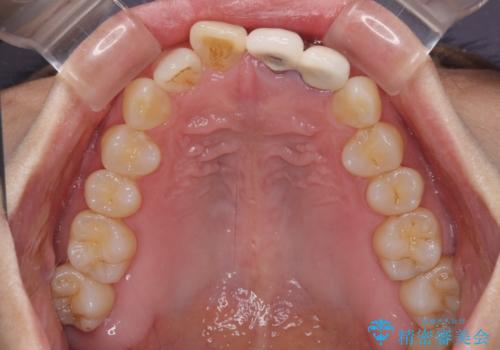

- 下顎前歯が抜けそうとのことで来院された患者様です。

初診の状態ではすぐにでも抜けそうな状態で、インプラントによる補綴治療を行うこととしました。

インプラント治療に際し、前歯の叢生に対する矯正治療を提案したところ、興味を持たれたので、インビザライン・ライトによる矯正治療を行うこととしました。

抜歯後にスペースができると恥ずかしいため、抜歯した歯を接着剤で固定した上で矯正治療を行い、その後インプラントやオールセラミッククラウンの装着を行うこととしました。